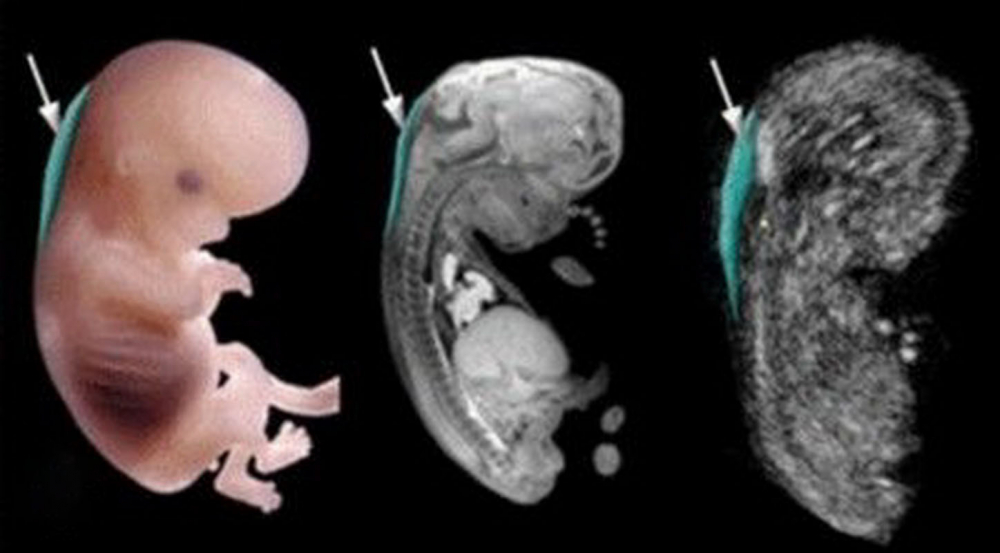

Определение толщины воротникового пространства (величина шейной складки, ТВП) — один из важнейших и довольно точных методов ранней диагностики хромосомных аномалий и других пороков развития. Именно этот эхографический маркер стал «золотым стандартом» на сроке 11—14 недель.

Общие сведения

Воротниковое пространство — это подкожное скопление жидкости в щелевидном участке между кожей, мышцами и связками на позвоночнике в задней части шеи. На УЗИ отображается как анэхогенная (черная) полоса. Оценка ТВП информативна на сроках от 11 до 14 недель, при КТР 45-84 мм, так как в дальнейшем скопление подкожной жидкости рассасывается.

Как выглядит на УЗИ

В начале исследования врач измеряет длину ребенка, то есть его КТР. Это крайне необходимо, потому что ТВП меняется в зависимости от срока беременности.

Потом эхографист выводит на экран верхнюю часть туловища и головку в боковой проекции, при этом в одном срезе должны быть одновременно кости и кожа спинки носа, полости 4 желудочка и кость верхней челюсти. Специалист увеличивает на мониторе область шеи. Затем измеряет наибольшую толщину скопления жидкости по задней поверхности шеи под кожей. Жидкость на экране окрашена черным цветом, а кожа и мягкие ткани — белым. После измерений врач сравнивает полученный результат с нормами.

Во время проведения измерения головка ребенка должна находиться в нейтральном положении. Если она слишком запрокинута назад, то можно получить завышенные измерения, и наоборот, если подбородок сильно поджат к груди, то измерения будут ниже реального значения.